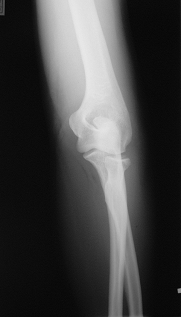

図8 a 図8 b

第24診時のレントゲン斜位像 第24診時のレントゲン正面像